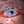

IMAGE OF THE WEEK

Acute hemorrhagic conjunctivitis.

Paul Hammond, OD, FAAO, @kmkoptometrypro